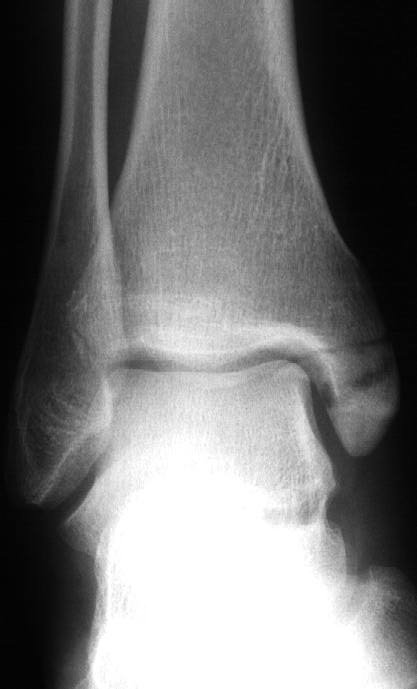

"Meanwhile, back on the route, Steph had decided to make the move, which involved reaching her right hand up to the left arete of the slab and, of course, the inevitable barndoor occurred. She pivoted balletically round the arete to fall down the other face, completely missing the expertly placed spotters and landing on the less well placed boulders below. She landed on her ankle and taken a slice off it against a rock which had also broken the bone and gouged it a bit. After convincing her that passing out was a bad idea we eventually managed to fireman's lift her to the car and the hospital where she had her ankle 'pinned'. As the x-ray shows it would have been more appropriate to call it 'screwed'."

Before having the pin After Side view with pin